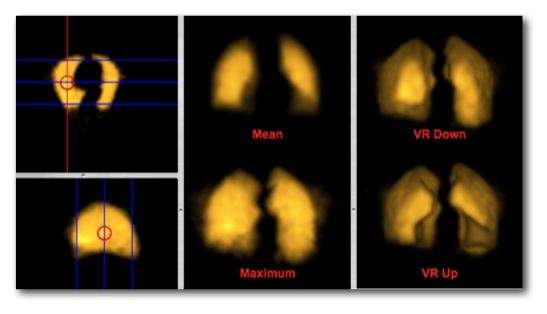

The figure below illustrates the outcome of a range of z-projection methods, with a single slice shown in the bottom right hand corner for reference purposes. The first image in the top left shows the result of summing 16 slices, and the other two images on that row show the results of computing the mean and median of these slices.

The first two images in the second row show the result of what are called a Maximum Intensity Projection (MIP) and a Minimum Intensity Projection (MinIP), respectively. A MIP evaluates each voxel along each line of voxels through the volume to determine the maximum voxel value and forms an image using the values so determined for each line. A MinIP uses the minimum voxel values, as illustrated in the following figure:

Notice that volume rendering can be applied from distal to proximal slices, as illustrated in our figure, as well as in the opposite direction, i.e. from proximal to distal slices. Hence the terms Volume Rendering Up and Volume Rendering Down used in our set of nine example images above.

The type of axial projection method appropriate to an individual patient study is dependent on the anatomical and/or functional information of relevance to the diagnostic process. Let's take the case of imaging contrast-filled blood vessels, for example, in our nine example images above. Note that a MIP can be used to give a visually-stunning impression of the vessel bed in the patient's lungs. There's little depth information in this projection, however, so that overlapping and underlying vessels can obscure lesions that might be present in blood vessels of interest. The application of this form of axial projection to angiography is therefore limited to studies where vessel overlap isn't an issue. The inclusion of voxel transparency and depth weighting in volume rendered images addresses this limitation of MIP processing.